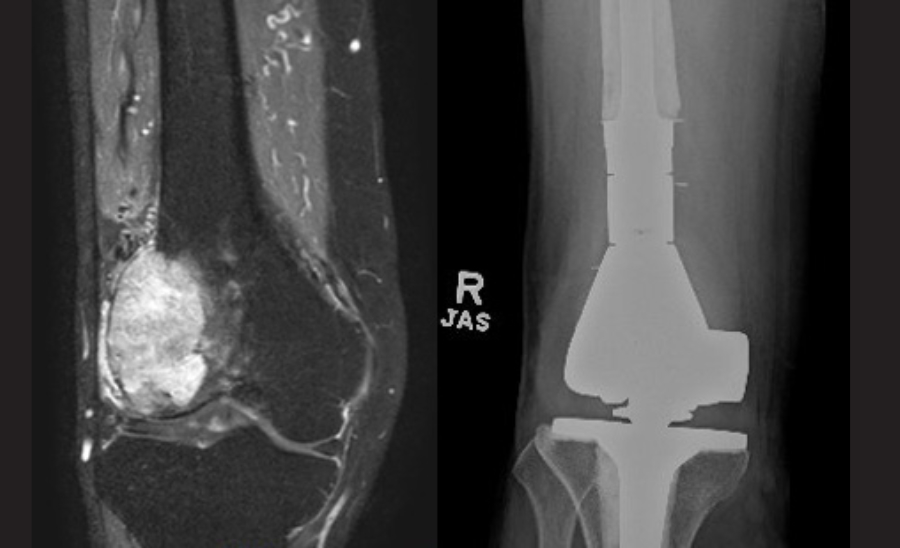

The aim of surgery is to prevent fractures from occurring, or to treat that fracture. A combination of clinical evaluation, X-rays and advanced scans are used to assess fracture risk. If the risk is estimated to be high, preventative surgery is offered, usually in the form of the insertion of a metal implant to reinforce the bone. Occasionally, the cancer affected segment of bone is removed and replaced with a metal implant; the complete removal of metastatic deposits (metastatectomy) reduces the risk of local cancer recurrence and may improve survival. The strategy is particularly useful if there is a single metastasis, the metastasis is poorly responsive to other forms of treatment, and/or if the patient has a long life expectancy. As cancer patients are now living for many years, it is important that the surgery should be sufficiently durable.

Figure 1: (L) An MRI of the right distal femur shows metastatic renal cell cancer. (R) A post-operative X-ray shows replacement of the bone with a tumour endoprosthesis. The implant allows the patient to walk immediately after surgery and provides a very durable reconstruction.